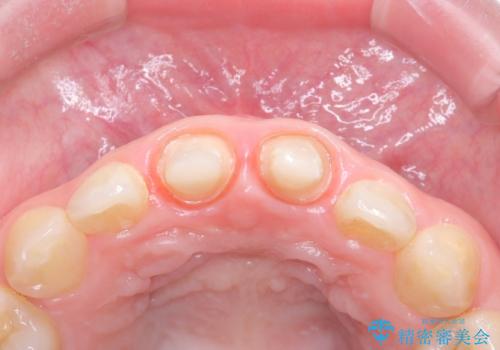

- 以前他院で治療した前歯の被せものの見た目の不満を主訴にご来院されました。レントゲンと診査の結果、被せものの不適合だけでなく、その土台となる歯の根管充填(根の治療の詰め物)が不十分であることが判明。再感染のリスクを避けるため、まず精密根管治療を行い、その後に最も審美性に優れたオールセラミッククラウンで修復する治療計画を立案しました。これにより、見た目の改善と歯の寿命の長期化を目指しました。

治療は、再感染の原因となっていた粗な根管充填材を丁寧に取り除く精密根管治療から開始しました。治療中はラバーダムと歯科用顕微鏡を使用し、根管内を徹底的に清掃・消毒。根の先まで緊密に薬を詰めることで、再発リスクを最小限に抑えました。根管治療の完了後、歯ぐきの状態を整え、周囲の歯と調和するオールセラミッククラウンを作製。金属を一切使わないため、透明感のある自然な仕上がりとなり、長年の見た目のコンプレックスも解消。歯の内部から表面までを根本的に改善することができました。